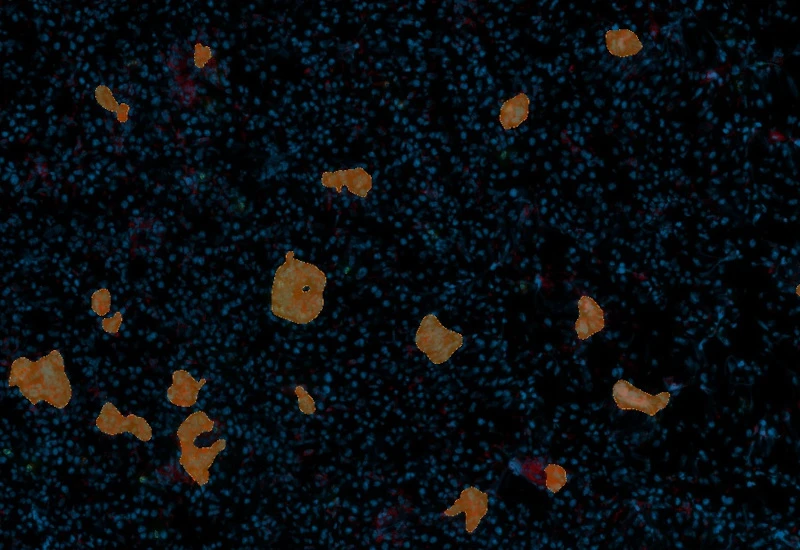

The IF Granuloma App detects granulomas based on nuclear structure analysis and an adequate IF staining (e.g. CD11c, CD68). The number and area of Granulomas as well as their density is measured. Each segmented cell compartment is measured for up to 20 intensity, statistic and morphometric parameters.

Granuloma detection

Granuloma detection and phenotyping